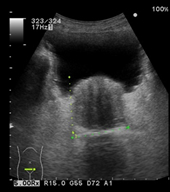

頸動脈の超音波検査

頸部にゼリーを塗り超音波をあてて、画面に頸動脈を映し出し血管壁や血流を観察します。

血管壁の厚さや血管壁にコレステロールなどが沈着したプラークと呼ばれる壁隆起の数、

大きさ、形状などを参考に動脈硬化の進行の程度や脳梗塞、心筋梗塞の発症の危険性を判定します。

正常頸動脈

動脈硬化が進行した頸動脈